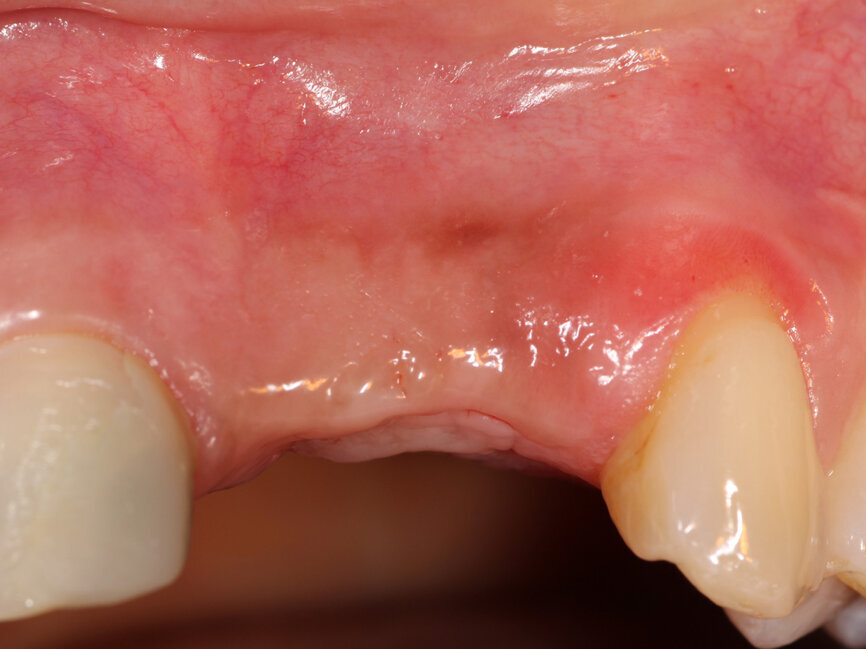

At 4.5 months post surgery the patient returned, and the soft tissue over and adjacent to the site demonstrated an absence of inflammation and appeared healthy with palpation of the grafted site feeling dense to the touch (Figs. 15a,b). A CBCT was taken to evaluate graft maturation and alterations to the ridge width as a result of grafting. A CBCT cross-section of the graft revealed incorporation of the graft and dimensional changes to the ridge width that would now allow implant placement (Fig. 16). Local anesthetic (2 percent lidocaine with 1:100,000 epinephrine) was administered to the site via infiltration and a full thickness flap was elevated. The graft was not discernable from the adjacent non-grafted bone and appeared dense to instrument touch and the defect was filled resulting in adequate width for implant placement (Fig. 17). Osteotomies were created to accommodate a 3.7 mm x 13 mm implant (ImplantVision, West Palm Beach, Fla.) at the left central site and a 3.2-by-13-mm implant at the left lateral site and implants were placed and cover screws attached (Fig. 18). The site was closed with 5-0 Polypropylene sutures in an interrupted pattern and the patient dismissed. Restoration of the implants would occur following a three- to five-month integration period. A CBCT taken following implant placement demonstrates adequate thickness of the facial bone at the implant to house the implant and allow long-term stability (Fig. 19).

Fig. 15a: The previously deficient ridge at the left central and lateral incisors resulting from resorption following the previously extracted teeth had been augmented and is ready for implant placement following 4.5 months of graft healing.

Fig. 15b: The previously deficient ridge at the left central and lateral incisors resulting from resorption following the previously extracted teeth had been augmented and is ready for implant placement following 4.5 months of graft healing.